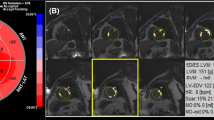

First, we marked the segments of the myocardial scar with the bull’s eye segmental comparison (17-segment model) and compared them with the results of coronary angiography. Second, we searched for the thickest myocardial scar layer-by-layer on the short axis imaging and calculated the percentage of the thickness of the myocardial scar, which was defined as a transmural myocardial scar when the percentage was > 75%, according to previous study [13]. Beek et al. demonstrated that the transmural extent is relevant in predicting myocardial functional recovery: The likelihood of complete functional recovery of segments without LGE was 3.8, 11.1, and 50 times higher than that of segments with 26–50%, 51–75%, and > 75% LGE, respectively (P < 0.001) [13]. Finally, we recorded the area of myocardial scar and calculated the percentage of myocardial scar volume by segment software.

Location, size, thickness of the myocardial scar determined by CMR-LGE

Myocardial scars were diagnosed in 41 of 42 STEMI patients (96.7%) by using CMR-LGE. A patient-by-patient visual analysis of scar tissue location in the STEMI group, with bull’s eye segmental comparison of CMR-LGE findings is shown in Additional file 1: Fig. S1. In all patients, the anatomic locations of scars defined by CMR-LGE corresponded to the distributions of the culprit vessels treated with primary angioplasty. For example, in a patient with angiographically proven left anterior descending coronary artery occlusion, CMR-LGE indicated scarification of the basal and middle segments of the left anterior ventricular wall. In another patient with right coronary artery occlusion, CMR-LGE disclosed a scar that involved the entire inferior wall of the left ventricle and the middle and apical segments of the posterior interventricular septum (Additional file 1: Fig. S2). However, scar size and thickness were unrelated to the degree of coronary artery occlusion. Stenoses in all culprit arteries exceeded 90%; nonetheless, there were significant inter-patient differences in scar size and thickness (P < 0.001).